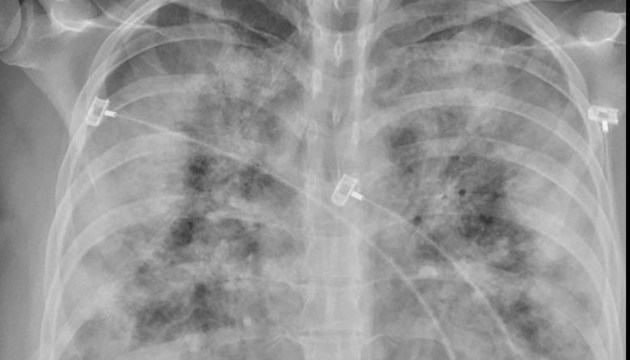

Вакцинация от Covid-19 полностью не защищает от заражения коронавирусом, однако различия заметны, если наблюдать за самим ходом болезни. Сравнение двух рентгеновских снимков ясно показывает, как это выражается по отношению к повреждениям легких.

Однако факт, что вакцины защищают, по-прежнему в силе. Поэтому те, кто вакцинирован и все-таки заразился коронавирусом, может считаться с куда более легким течением болезни, чем невакцинированные лица. То, насколько велико различие, наглядно видно на сравнении двух рентгеновских снимков.

На рентгеновских снимках, которыми в Twitter поделился руководитель отдела инфекционных заболеваний Университета Мэриленда Фахим Йоунус, можно увидеть очень разные легкие. В обоих случаях это легкие пациентов, зараженных Covid-19, однако на одном снимке видно гораздо больше светлых теней, чем на втором. Белые тени - так называемое "матовое стекло", возникающее при воспалении легких. Если в тканях накапливается вода, то на рентгеновских снимках она видна как "светлые облака". На втором снимке легких такого эффекта практически нет. Это легкие вакцинированного от Covid-19 человека, который очевидно лучше перенес инфекцию.